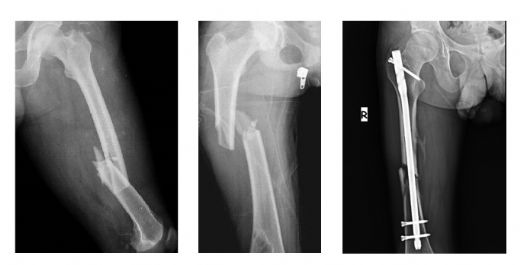

Kemik Onarımı

Kemik zarı, kemik yaralanmaları ve kırıkları sonrası onarım sürecinde de önemli bir görev üstlenir. Yaralanma durumunda, kemik zarındaki osteoblastlar ve osteoklastlar devreye girerek hasar gören bölgenin iyileşmesini sağlar.

• Osteoblastlar, yeni kemik dokusu oluştururken, osteoklastlar eski ve hasarlı kemik dokusunu parçalayarak yeni kemik oluşumuna zemin hazırlar.

• Kemik zarı, yaralanma sonrası doku iyileşmesini destekleyen büyüme faktörleri ve sitokinler üretir.